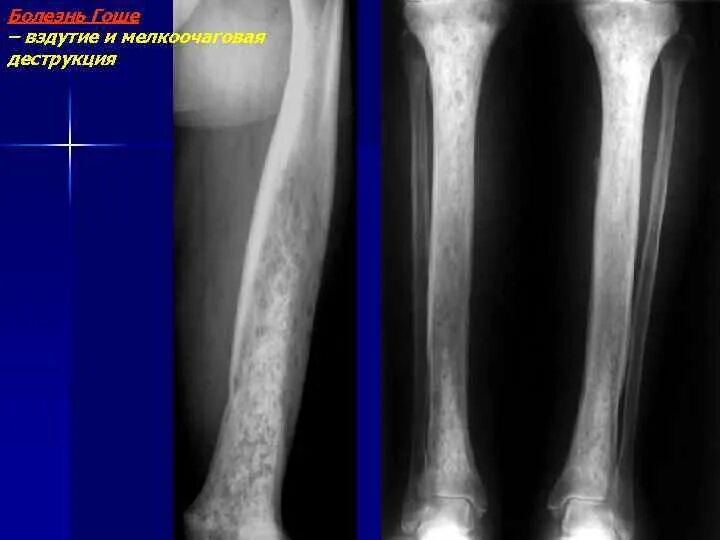

Костные структуры с дистрофическими изменениями